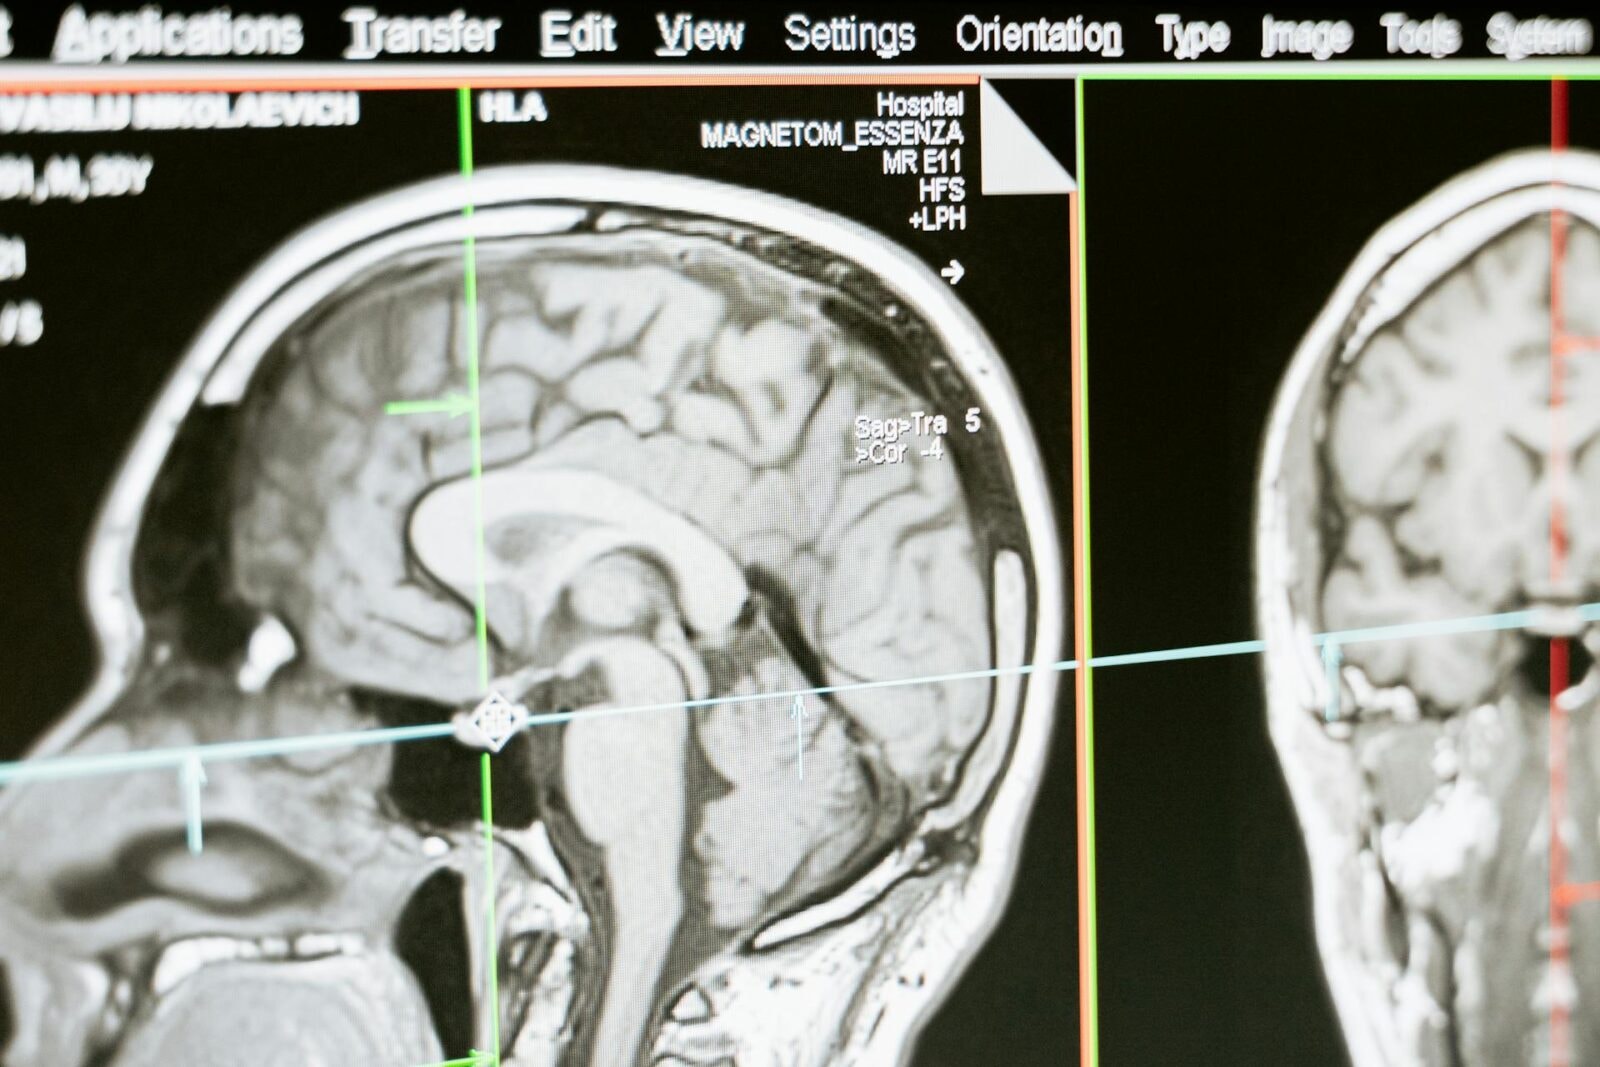

Ponieważ w momencie rozpoznania, guz prawdopodobnie jest mocno rozprzestrzeniony w mózgu, zmieniona tkanka jest niezwykle trudna do usunięcia. Chirurdzy podejmują się tego tylko wtedy, gdy mają pewność, że zabieg nie wpłynie na funkcjonowanie mózgu. Skala zmian jest bardzo trudna do oszacowania, bo mikrowłókna glejaka mogą rozprzestrzenić się na cały mózg, czego nie wykryje nawet rezonans magnetyczny. Nawet po usunięciu guza, glejak może powrócić.